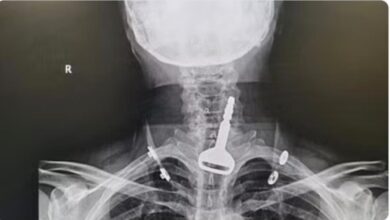

استخراج مفتاح سيارة من الجهاز التنفسي لمريض بالقنفذة

أحوال – متابعات – معدي آل حيه: بحمد الله تعالى وتوفيقه نجح فريق طبي بمحافظة القنفذة في استخراج مفتاح سيارة من الجهاز التنفسي لمريض كاد أن يودي بحياته، في عملية…